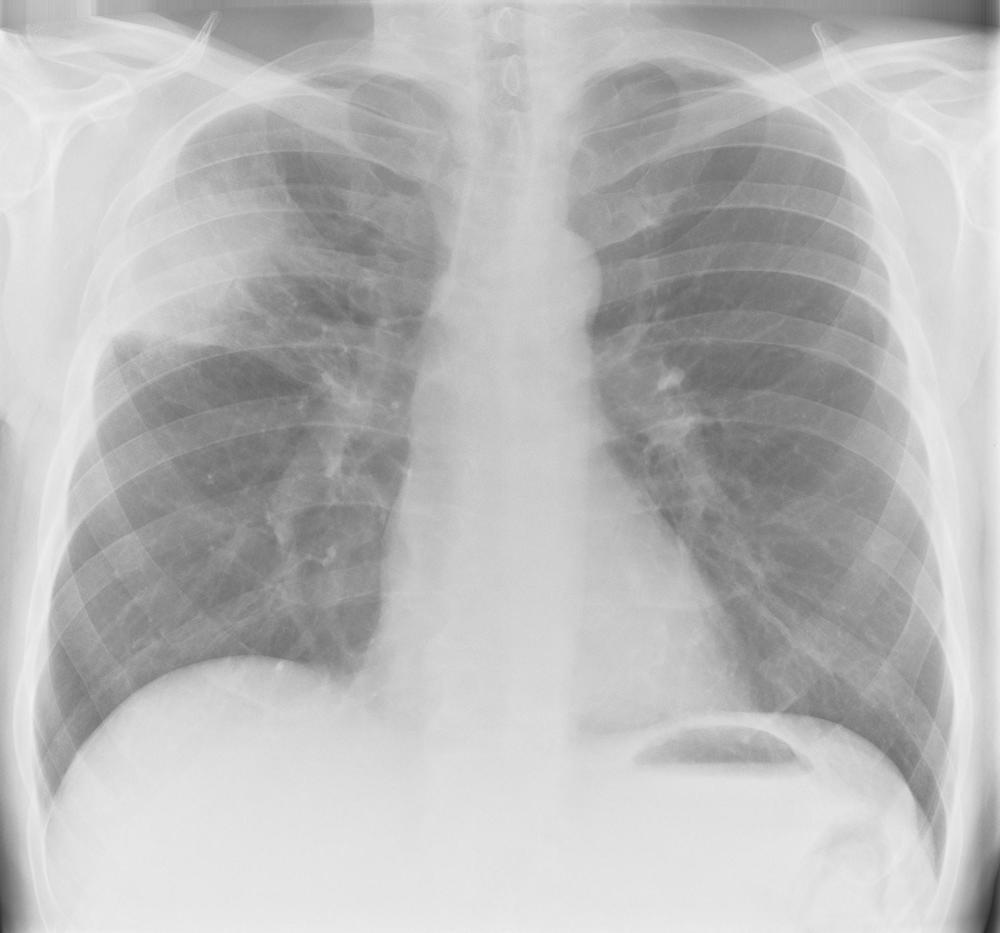

what does this CXR show?

A

simple pneumothorax

- visible rim of air between lung margin + chest wall

- no visible lung markings